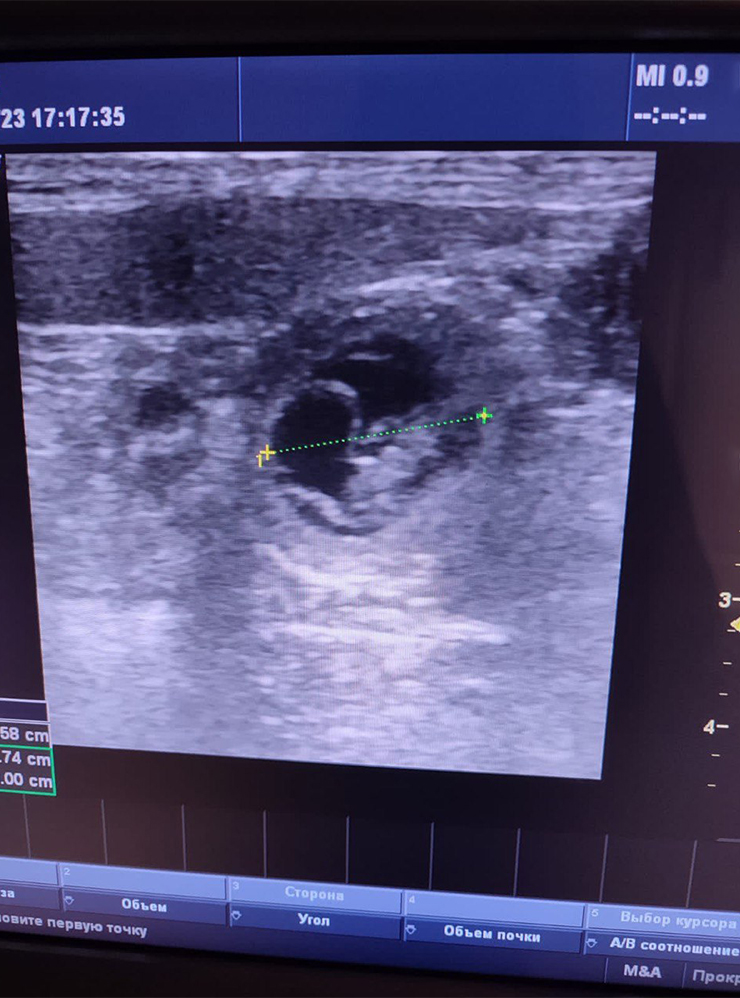

Чтобы подтвердить беременность у собак, с 21—25-го дня после предполагаемой овуляции или вязки ветеринары проводят УЗИ брюшной полости. А ближе к концу беременности — после 45-го дня — обычно делают рентген, чтобы посчитать щенков.

Отведите собаку на УЗИ через 21—25 дней после предполагаемого оплодотворения, чтобы подтвердить беременность и убедиться, что с питомицей и ее будущим потомством все в порядке.

Врач может увидеть плодные пузыри и эмбрионы, зафиксировать сердцебиение, оценить состояние матки и выявить признаки воспалительных изменений. Кроме того, именно на этом этапе можно заподозрить ранние осложнения, которые клинически никак себя не проявляют.